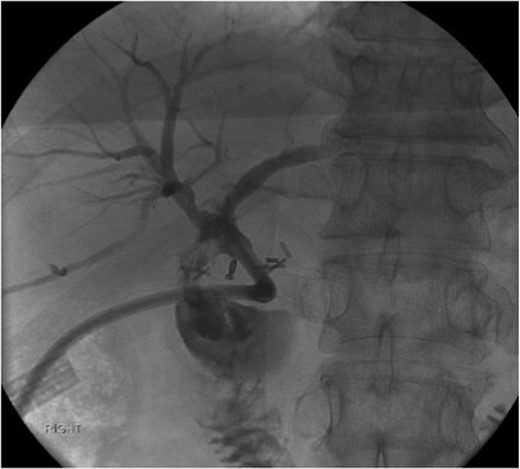

The labs on admission revealed a normal CMP and CBC, a slightly elevated alkaline phosphatase of 171 U/L (reference normal 34–104 U/L), normal aspartate transaminase and alanine transaminase levels, and a normal direct and total bilirubin of 0.2 and 0.5 mg/dL, respectively. A CT of the patient’s abdomen showed the external biliary drain within the CBD and no intra-abdominal fluid collections or intrahepatic biliary dilations. A cholangiogram showed a fistulous connection between the proximal CBD and the duodenum (Fig. 1). An elective choledochoduodenal fistula takedown and Roux-en-Y hepaticojejunostomy were performed.

Cholangiogram through the external catheter demonstrating a fistula between the common bile duct, just below the confluence of the right and left hepatic ducts at the terminal end of the catheter, and the duodenum.